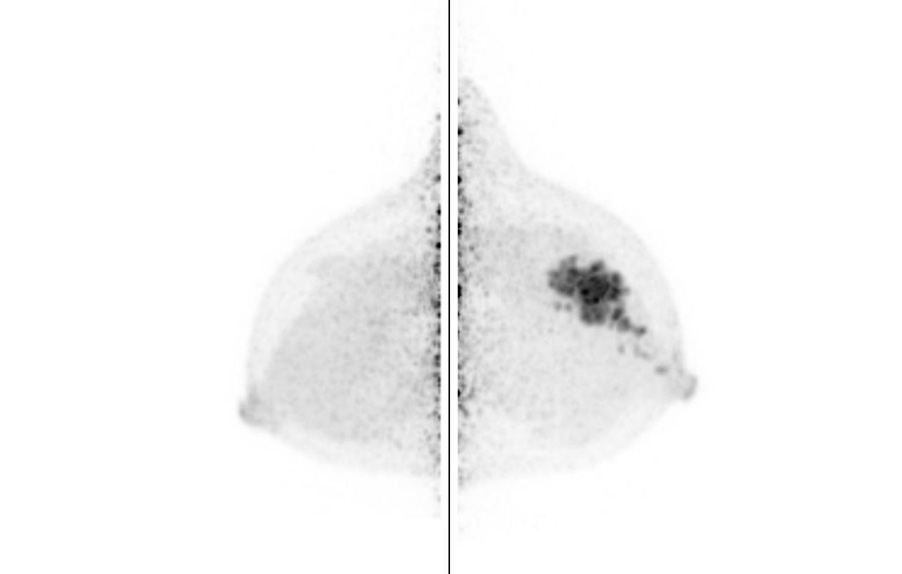

Breast / Case1 : FDG

ML-MIP

Courtesy : Kindai University Hospital

- Imaging protocol

- Injected dose: 2.64 MBq/kg, 18F-FDG

- Scan time: 5 minutes